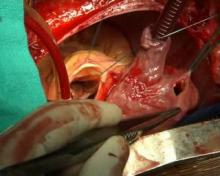

Repair of Ruptured Sinus of Valsalva Aneurysm [1] Featured Image: Author(s): A. Sampath Kumar, MDBy A. Sampath Kumar, MD Video: Content Area(s): Videos - General [3]